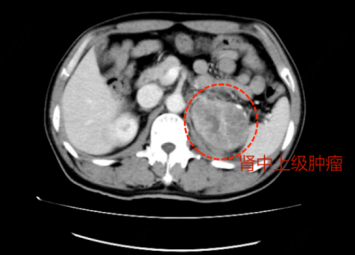

术前关:对于恶性肿瘤患者,一旦发现多为中晚期,检查后发现已错过最佳手术时机,而陈大叔因为术后复发,肿瘤情况进一步恶化,如果不积极外科手术干预身体可能会更糟。入院后王甫剑主任为大叔做全面的术前检查,腹部增强CT显示左肾中极肿瘤大小约8cm×6cm,与腰大肌粘连固定,且不排除肾静脉癌栓存在。为充分评估陈大叔术前病情,泌尿外科王甫剑主任汇报院领导,组织了多学科会诊,经各位专家讨论后,最终决定我院组织最强团队全力以赴为陈大叔准备手术。考虑到患者肿瘤体积大,直接采取肿瘤切除术的风险较高,为减少术中出血,预防癌栓脱落,术前介入科陈育锋主任为患者先行左肾肿瘤动脉及左肾付肾动脉栓塞术,防止术中大出血及肿瘤癌栓的脱落,可有效降低手术风险,为手术提供保障。

手术关:一切准备就绪,2023-09-19上午陈大叔被推入手术室,无影灯下麻醉郑见、彭鹏二位主任、最强护理团队按预定手术方案有条不紊的进行操作。术中见左肾中上极可及8cm×6cm肿块,由于肿瘤周围粘连范围大,肾脏移动度极差,加之瘤体巨大,手术操作空间小,大大增加了手术难度,需要非常谨慎以免误伤周围脏器和肠管,在普外科冯兴波副主任医师的协助下,历经近2小时30分,左肾肿瘤、左肾上腺以及肾周组织、上段输尿管及转移到腰大肌的肿瘤及部分腰大肌组织一并完整切除干净,陈大叔顺利度过手术关。